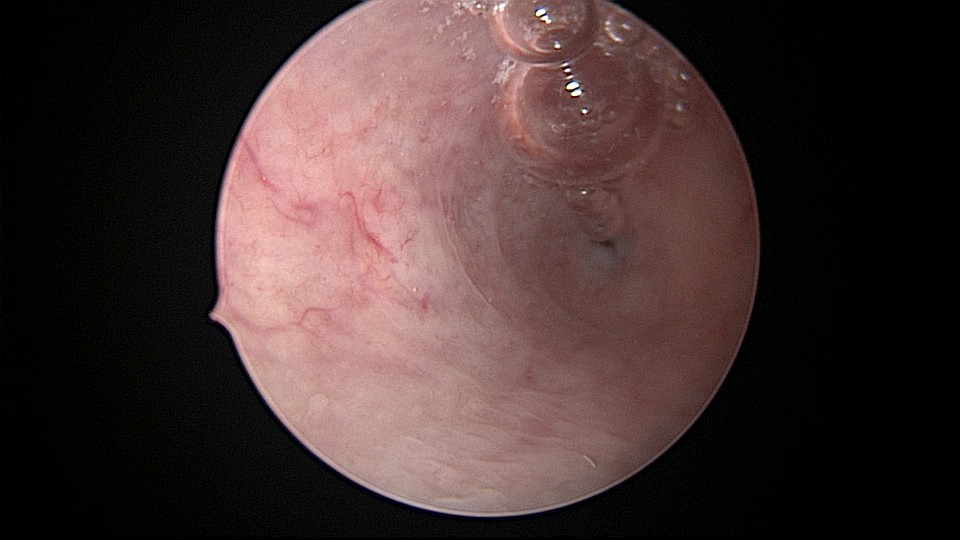

患者32岁,G2P0,自然流产2次,外院行清宫术,术后月经量减少一半。2019年6月市妇幼分粘,术后月经无改善,宫腔粘连复发,2020年11月宫腔镜探查,宫腔中上段幕状粘连,形成两个假的输卵管开口,双极电针分粘,恢复宫腔形态,显露正常的输卵管开口。2020年12月宫腔镜二探取球囊,宫腔形态正常,双侧输卵管开口可见,内膜充血。2022年5月自然妊娠,2023年1月剖宫产分娩一女婴(37+2)。现37岁,G3P1。